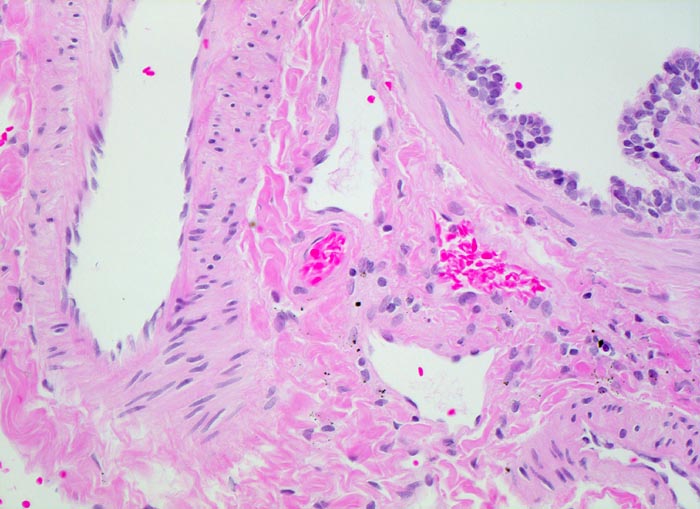

Morphologische Merkmale:

• Zwei Bronchuslichtungen. Eine davon verschlossen durch einen Tumorzapfen.

• Infiltration und Destruktion der Bronchialwand.

• Solide Zellstränge eingebettet in lockeres desmoplastisches Stroma.

• Im Zentrum der Zellstränge grosse Mengen von teils nekrotisch zerfallenden Hornlamellen und Fremdkörperriesenzellen.

• Zytoplasmareiche Tumorzellen mit stachelartigen Interzellularbrücken.

• Vergrösserte hyperchromatische Kerne.

• Mitosen.